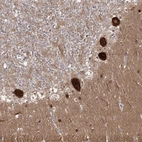

Immunohistochemical staining of human cerebellum shows strong cytoplasmic positivity in purkinje cells.